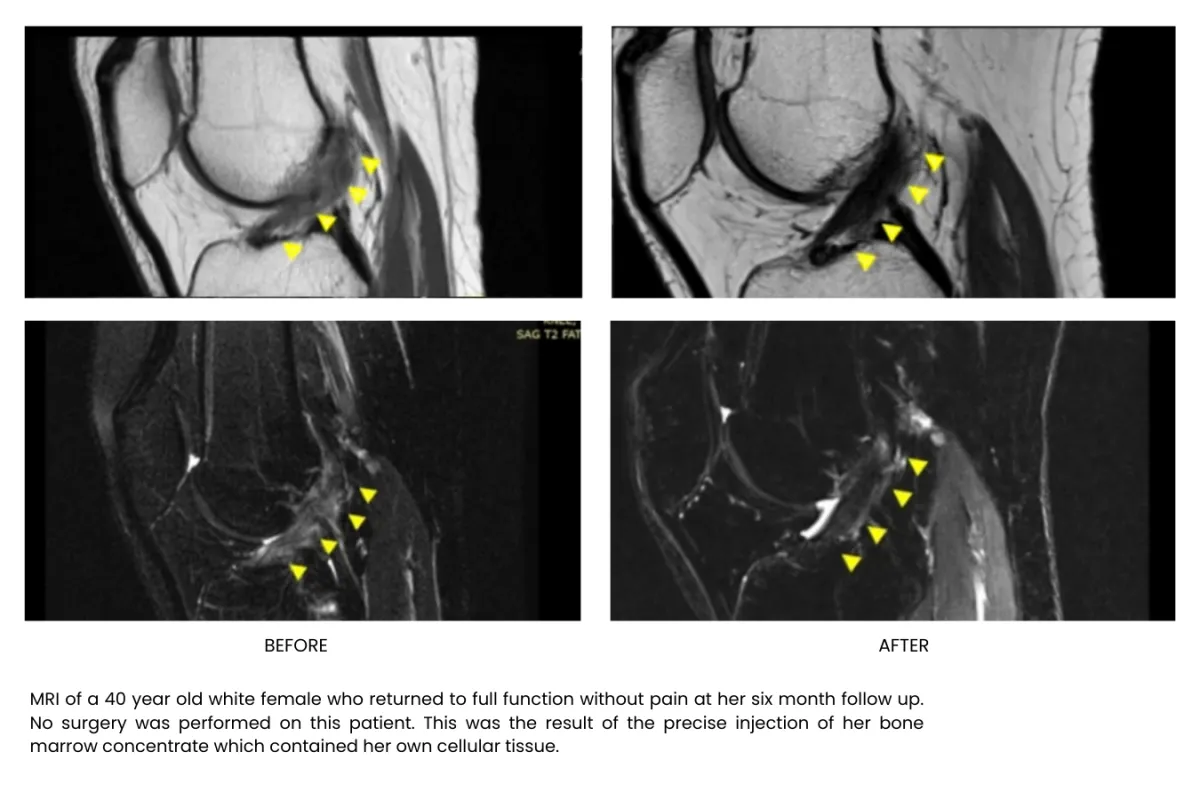

Millions of stem cells delivered precisely in the injured area building up tissue, recovering and freeing your from pain, without surgery or long recoveries.

Stem cell therapy is a regenerative treatment that uses specialized healing cells to help repair damaged tissue, reduce inflammation, and support your body’s natural healing process. It’s commonly used for joint pain, arthritis, and chronic musculoskeletal conditions.